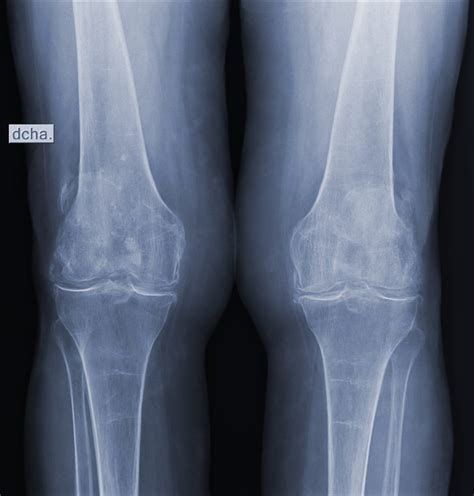

Pruebas de Imagen

- Radiografía simple: útil para descartar otras patologías como fracturas, focos de osteomielitis o tumores, y puede mostrar signos indirectos de infección articular.